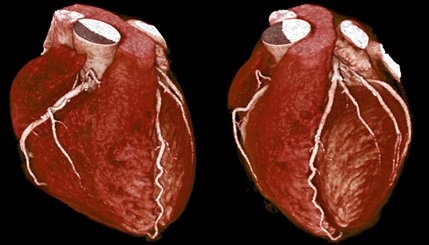

● 極高速:掃描心臟一圈僅0.275秒,比上一代快20%,大幅縮短檢查時間

這麼快的速度使得大部分受檢者不必服用藥物來降低心跳以進行心臟檢查,並具有更加清晰的影像品質,可應用於心血管疾病,腫瘤篩檢,以及其他全身應用。憑藉卓越的影像品質,幫助醫生準確診斷,進而給患者及時的治療。低輻射劑量、低顯影劑用量、大範圍一次性動態成像,配載獨家獨家AI人工智能軟體,可同時檢查多器官疾病等特點,且由於放射線對人體的損傷減少,檢查速度提高,檢查舒適度也大為改善;對受檢民眾是一大福音。

近年來影像學的發展一日千里,在健康檢查上,以非侵入性的多排式的電腦斷層術及磁振造影,來偵測心臟及腦血管疾病以預防猝死的重要性愈來愈高;像是冠狀動脈狹窄、主動脈瘤或腦動脈瘤的存在等,都可因事先偵測出來,進而預防因阻塞引起心肌梗塞,或是因血管破裂而引起的休克或腦死。